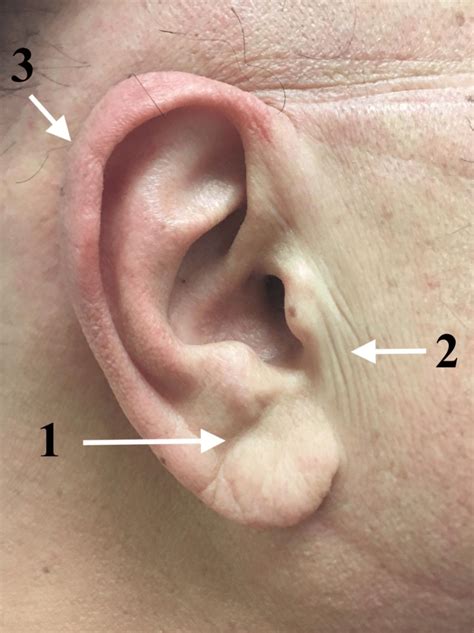

The preauricular region is a complex anatomical area characterized by its proximity to critical facial structures. Precise knowledge of underlying anatomy is crucial for safe and effective filler placement. This zone comprises several key elements:

- Thin, delicate skin with minimal fat deposits

- Close proximity to facial nerve branches

- Unique bone and soft tissue contours

- Significant impact on overall facial symmetry and balance